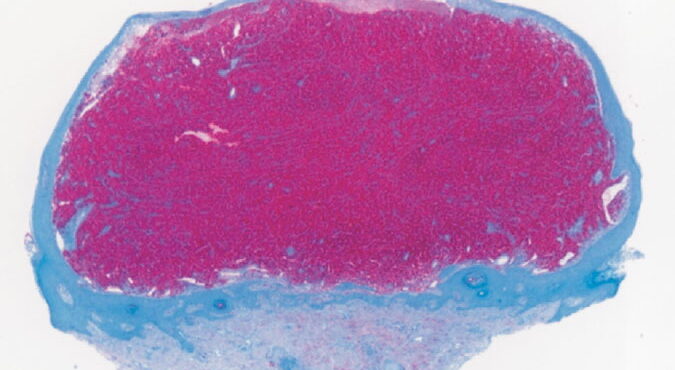

Epidermolysis bullosa acquisita = انحلال البشرة الفقاعي المكتسب Epidermolysis Bullosa Acquisita Classically, EBA is a noninherited disorder of acquired skin fragility. This presentation of EBA was the only one recognized until later. Blisters develop on noninflammatory bases with a predilection for acral areas. Scarring and milia formation ensue. A characteristic nail dystrophy and alopecia are […]